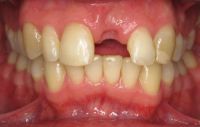

Voor de behandeling

Gebitsslijtage door een eetstoornis op jeugdige leeftijd. Door het vele spugen is er heel vaak maagzuur langs de tanden en kiezen gekomen waardoor bijna de gehele binnenzijde van de tanden is opgelost. Doordat de tanden zo dun zijn geworden, breken er gemakkelijk stukjes vanaf.